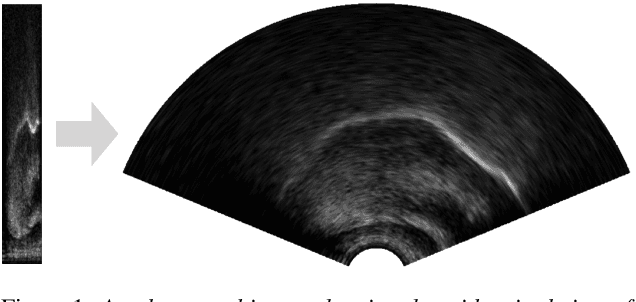

Abstract:Speech sound disorder (SSD) is defined as a persistent impairment in speech sound production leading to reduced speech intelligibility and hindered verbal communication. Early recognition and intervention of children with SSD and timely referral to speech and language therapists (SLTs) for treatment are crucial. Automated detection of speech impairment is regarded as an efficient method for examining and screening large populations. This study focuses on advancing the automatic diagnosis of SSD in early childhood by proposing a technical solution that integrates ultrasound tongue imaging (UTI) with deep-learning models. The introduced FusionNet model combines UTI data with the extracted texture features to classify UTI. The overarching aim is to elevate the accuracy and efficiency of UTI analysis, particularly for classifying speech sounds associated with SSD. This study compared the FusionNet approach with standard deep-learning methodologies, highlighting the excellent improvement results of the FusionNet model in UTI classification and the potential of multi-learning in improving UTI classification in speech therapy clinics.

Abstract:Ultrasound tongue imaging is used to visualise the intra-oral articulators during speech production. It is utilised in a range of applications, including speech and language therapy and phonetics research. Ultrasound and speech audio are recorded simultaneously, and in order to correctly use this data, the two modalities should be correctly synchronised. Synchronisation is achieved using specialised hardware at recording time, but this approach can fail in practice resulting in data of limited usability. In this paper, we address the problem of automatically synchronising ultrasound and audio after data collection. We first investigate the tolerance of expert ultrasound users to synchronisation errors in order to find the thresholds for error detection. We use these thresholds to define accuracy scoring boundaries for evaluating our system. We then describe our approach for automatic synchronisation, which is driven by a self-supervised neural network, exploiting the correlation between the two signals to synchronise them. We train our model on data from multiple domains with different speaker characteristics, different equipment, and different recording environments, and achieve an accuracy >92.4% on held-out in-domain data. Finally, we introduce a novel resource, the Cleft dataset, which we gathered with a new clinical subgroup and for which hardware synchronisation proved unreliable. We apply our model to this out-of-domain data, and evaluate its performance subjectively with expert users. Results show that users prefer our model's output over the original hardware output 79.3% of the time. Our results demonstrate the strength of our approach and its ability to generalise to data from new domains.

Abstract:Speech sound disorders are a common communication impairment in childhood. Because speech disorders can negatively affect the lives and the development of children, clinical intervention is often recommended. To help with diagnosis and treatment, clinicians use instrumented methods such as spectrograms or ultrasound tongue imaging to analyse speech articulations. Analysis with these methods can be laborious for clinicians, therefore there is growing interest in its automation. In this paper, we investigate the contribution of ultrasound tongue imaging for the automatic detection of speech articulation errors. Our systems are trained on typically developing child speech and augmented with a database of adult speech using audio and ultrasound. Evaluation on typically developing speech indicates that pre-training on adult speech and jointly using ultrasound and audio gives the best results with an accuracy of 86.9%. To evaluate on disordered speech, we collect pronunciation scores from experienced speech and language therapists, focusing on cases of velar fronting and gliding of /r/. The scores show good inter-annotator agreement for velar fronting, but not for gliding errors. For automatic velar fronting error detection, the best results are obtained when jointly using ultrasound and audio. The best system correctly detects 86.6% of the errors identified by experienced clinicians. Out of all the segments identified as errors by the best system, 73.2% match errors identified by clinicians. Results on automatic gliding detection are harder to interpret due to poor inter-annotator agreement, but appear promising. Overall findings suggest that automatic detection of speech articulation errors has potential to be integrated into ultrasound intervention software for automatically quantifying progress during speech therapy.

Abstract:We introduce UltraSuite, a curated repository of ultrasound and acoustic data, collected from recordings of child speech therapy sessions. This release includes three data collections, one from typically developing children and two from children with speech sound disorders. In addition, it includes a set of annotations, some manual and some automatically produced, and software tools to process, transform and visualise the data.